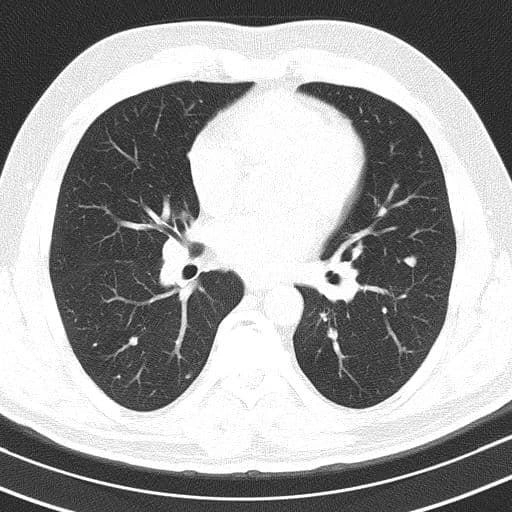

Врач прикрепил к посту фотографии легких больного с двухсторонней пневмонией и для сравнения легкие здорового человека.